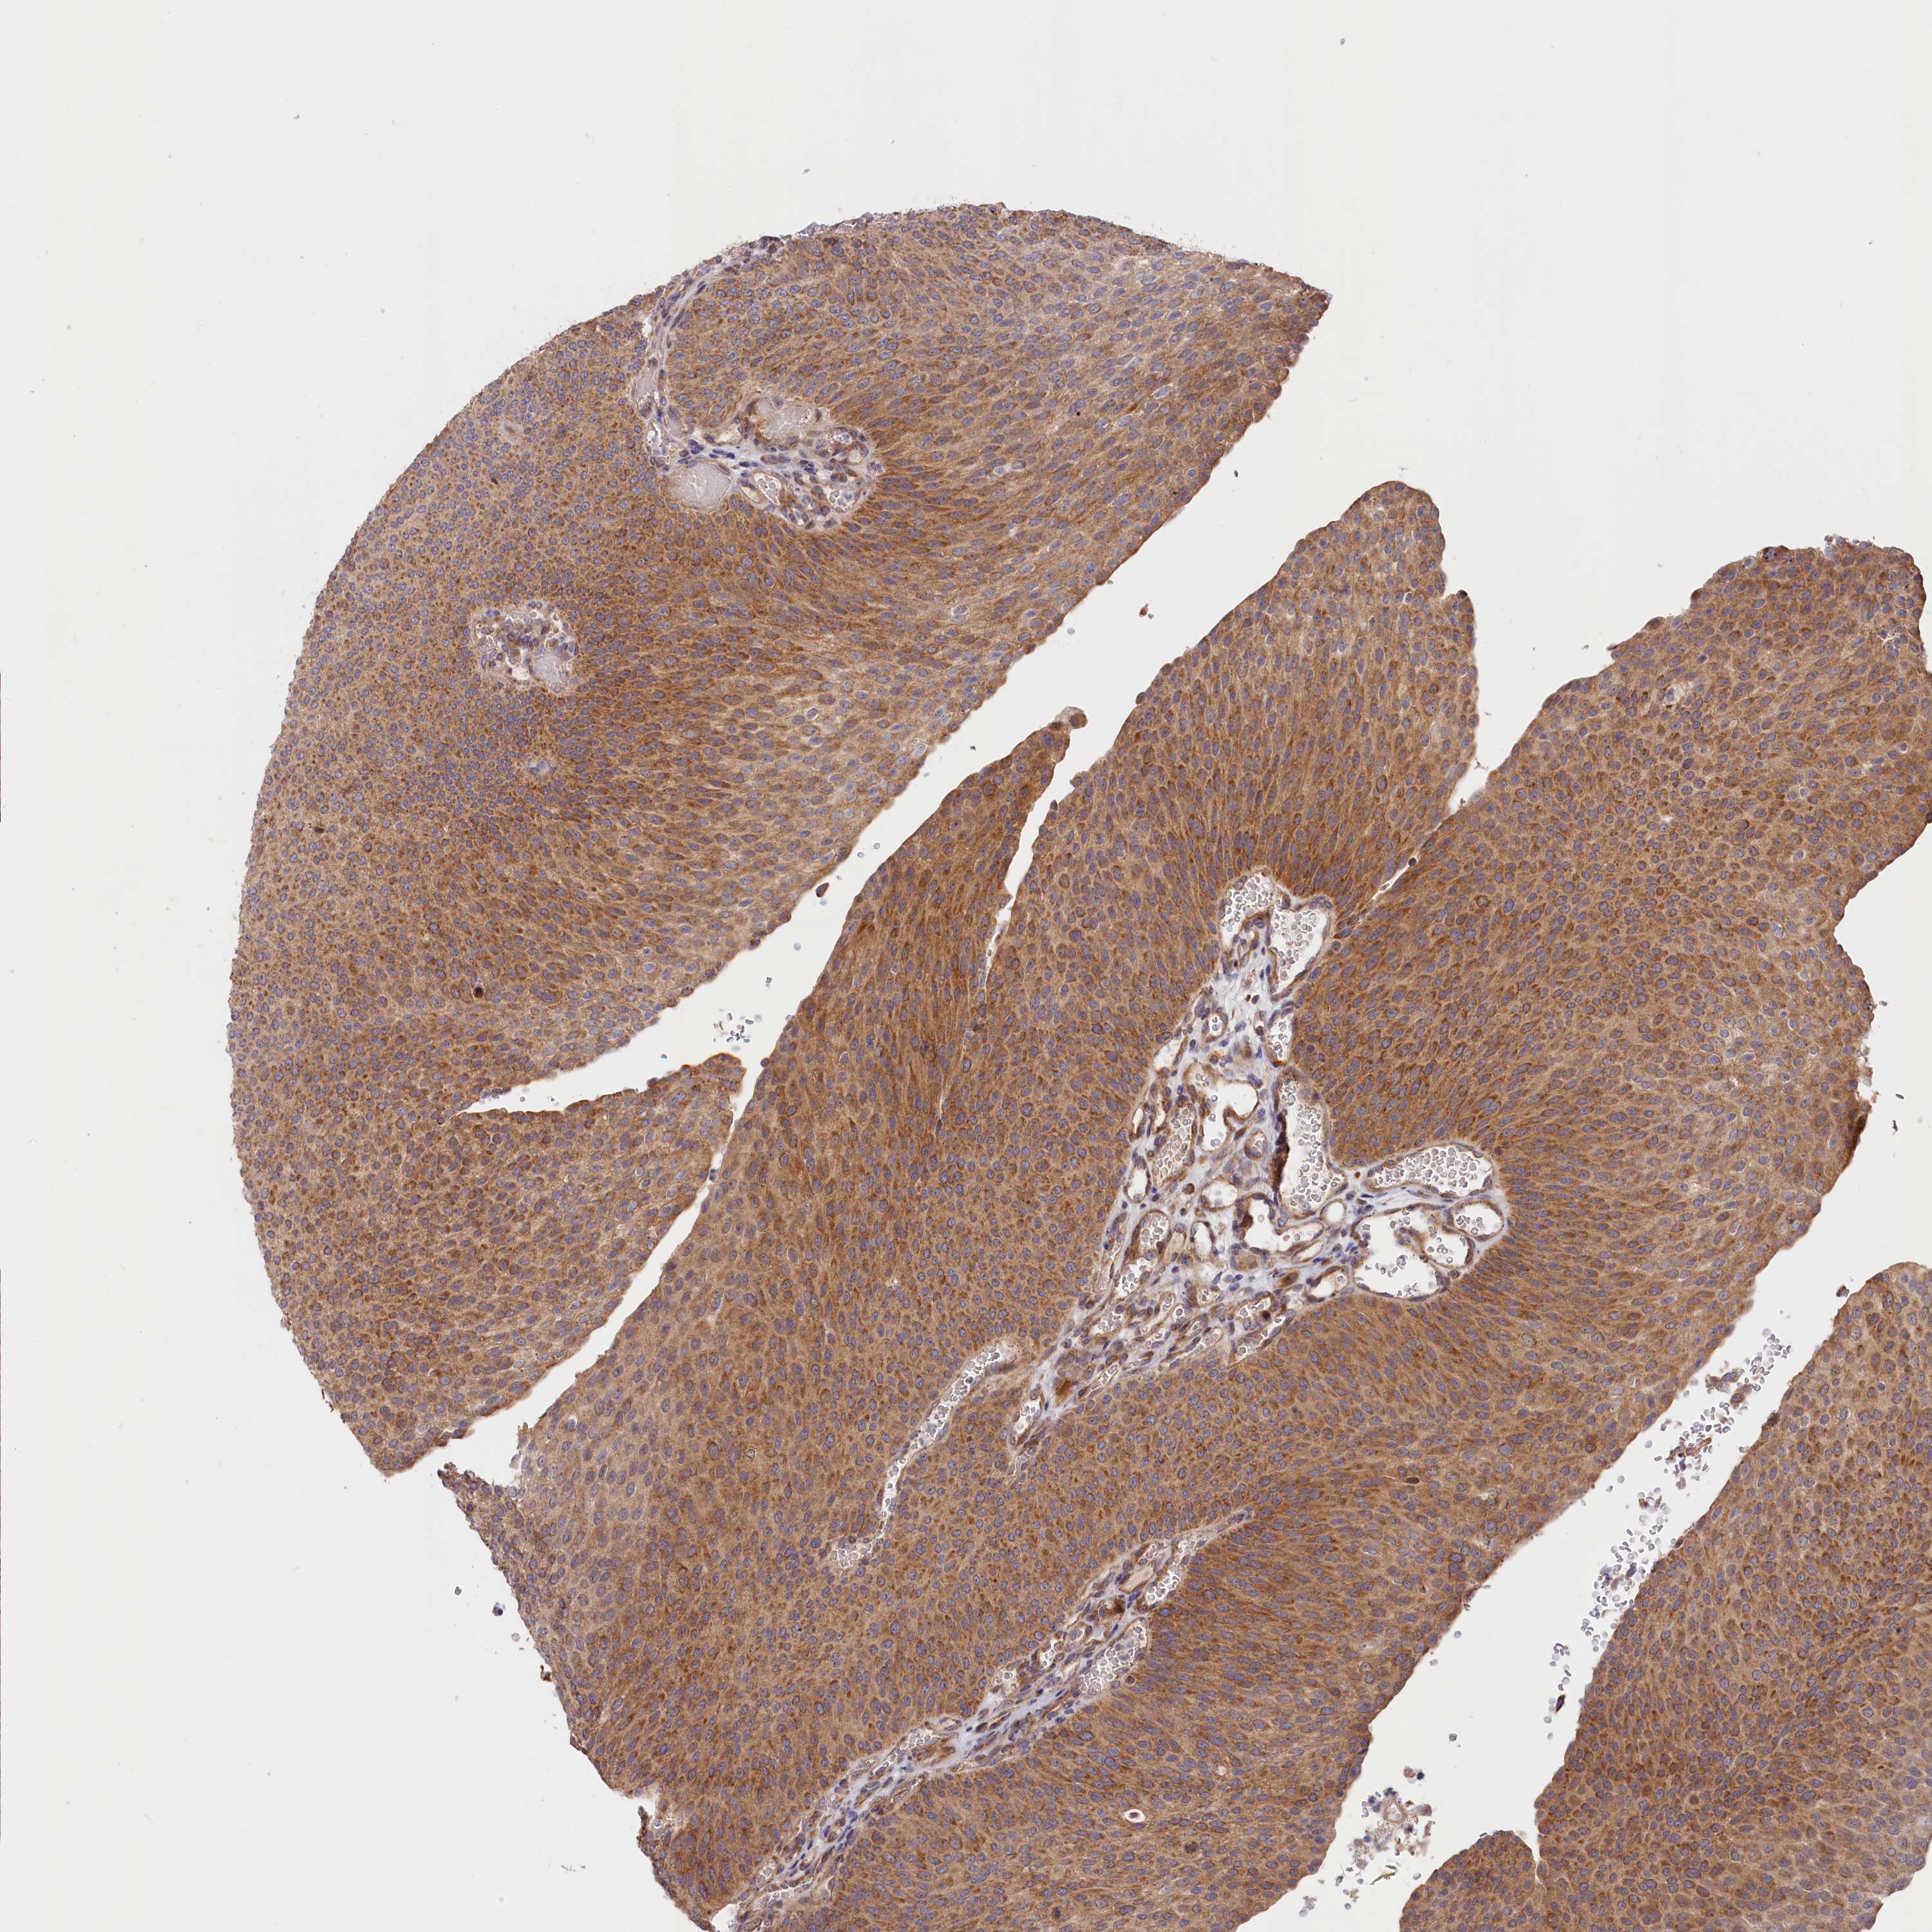

UROTHELIAL CANCER - Protein expressioni

A mouse-over function shows sample information and annotation data. Click on an image to view it in a full screen mode. Samples can be filtered based on level of antibody staining by selecting one or several of the following categories: high, medium, low and not detected. The assay and annotation is described here.

Note that samples used for immunohistochemistry by the Human Protein Atlas do not correspond to samples in the TCGA dataset.

Antibody stainingi

Antibody staining in the annotated cell types in the current human tissue is reported as not detected, low, medium, or high, based on conventional immunohistochemistry profiling in selected tissues. This score is based on the combination of the staining intensity and fraction of stained cells.

Each image is clickable and will lead to virtual microscopy that enables deeper exploration of all samples and also displays staining intensity scores, fraction scores and subcellular localization as well as patient and tissue information for each sample.

Antibody HPA041515

Antibody HPA041835

Urothelial carcinoma, High grade

Urothelial carcinoma, Low grade